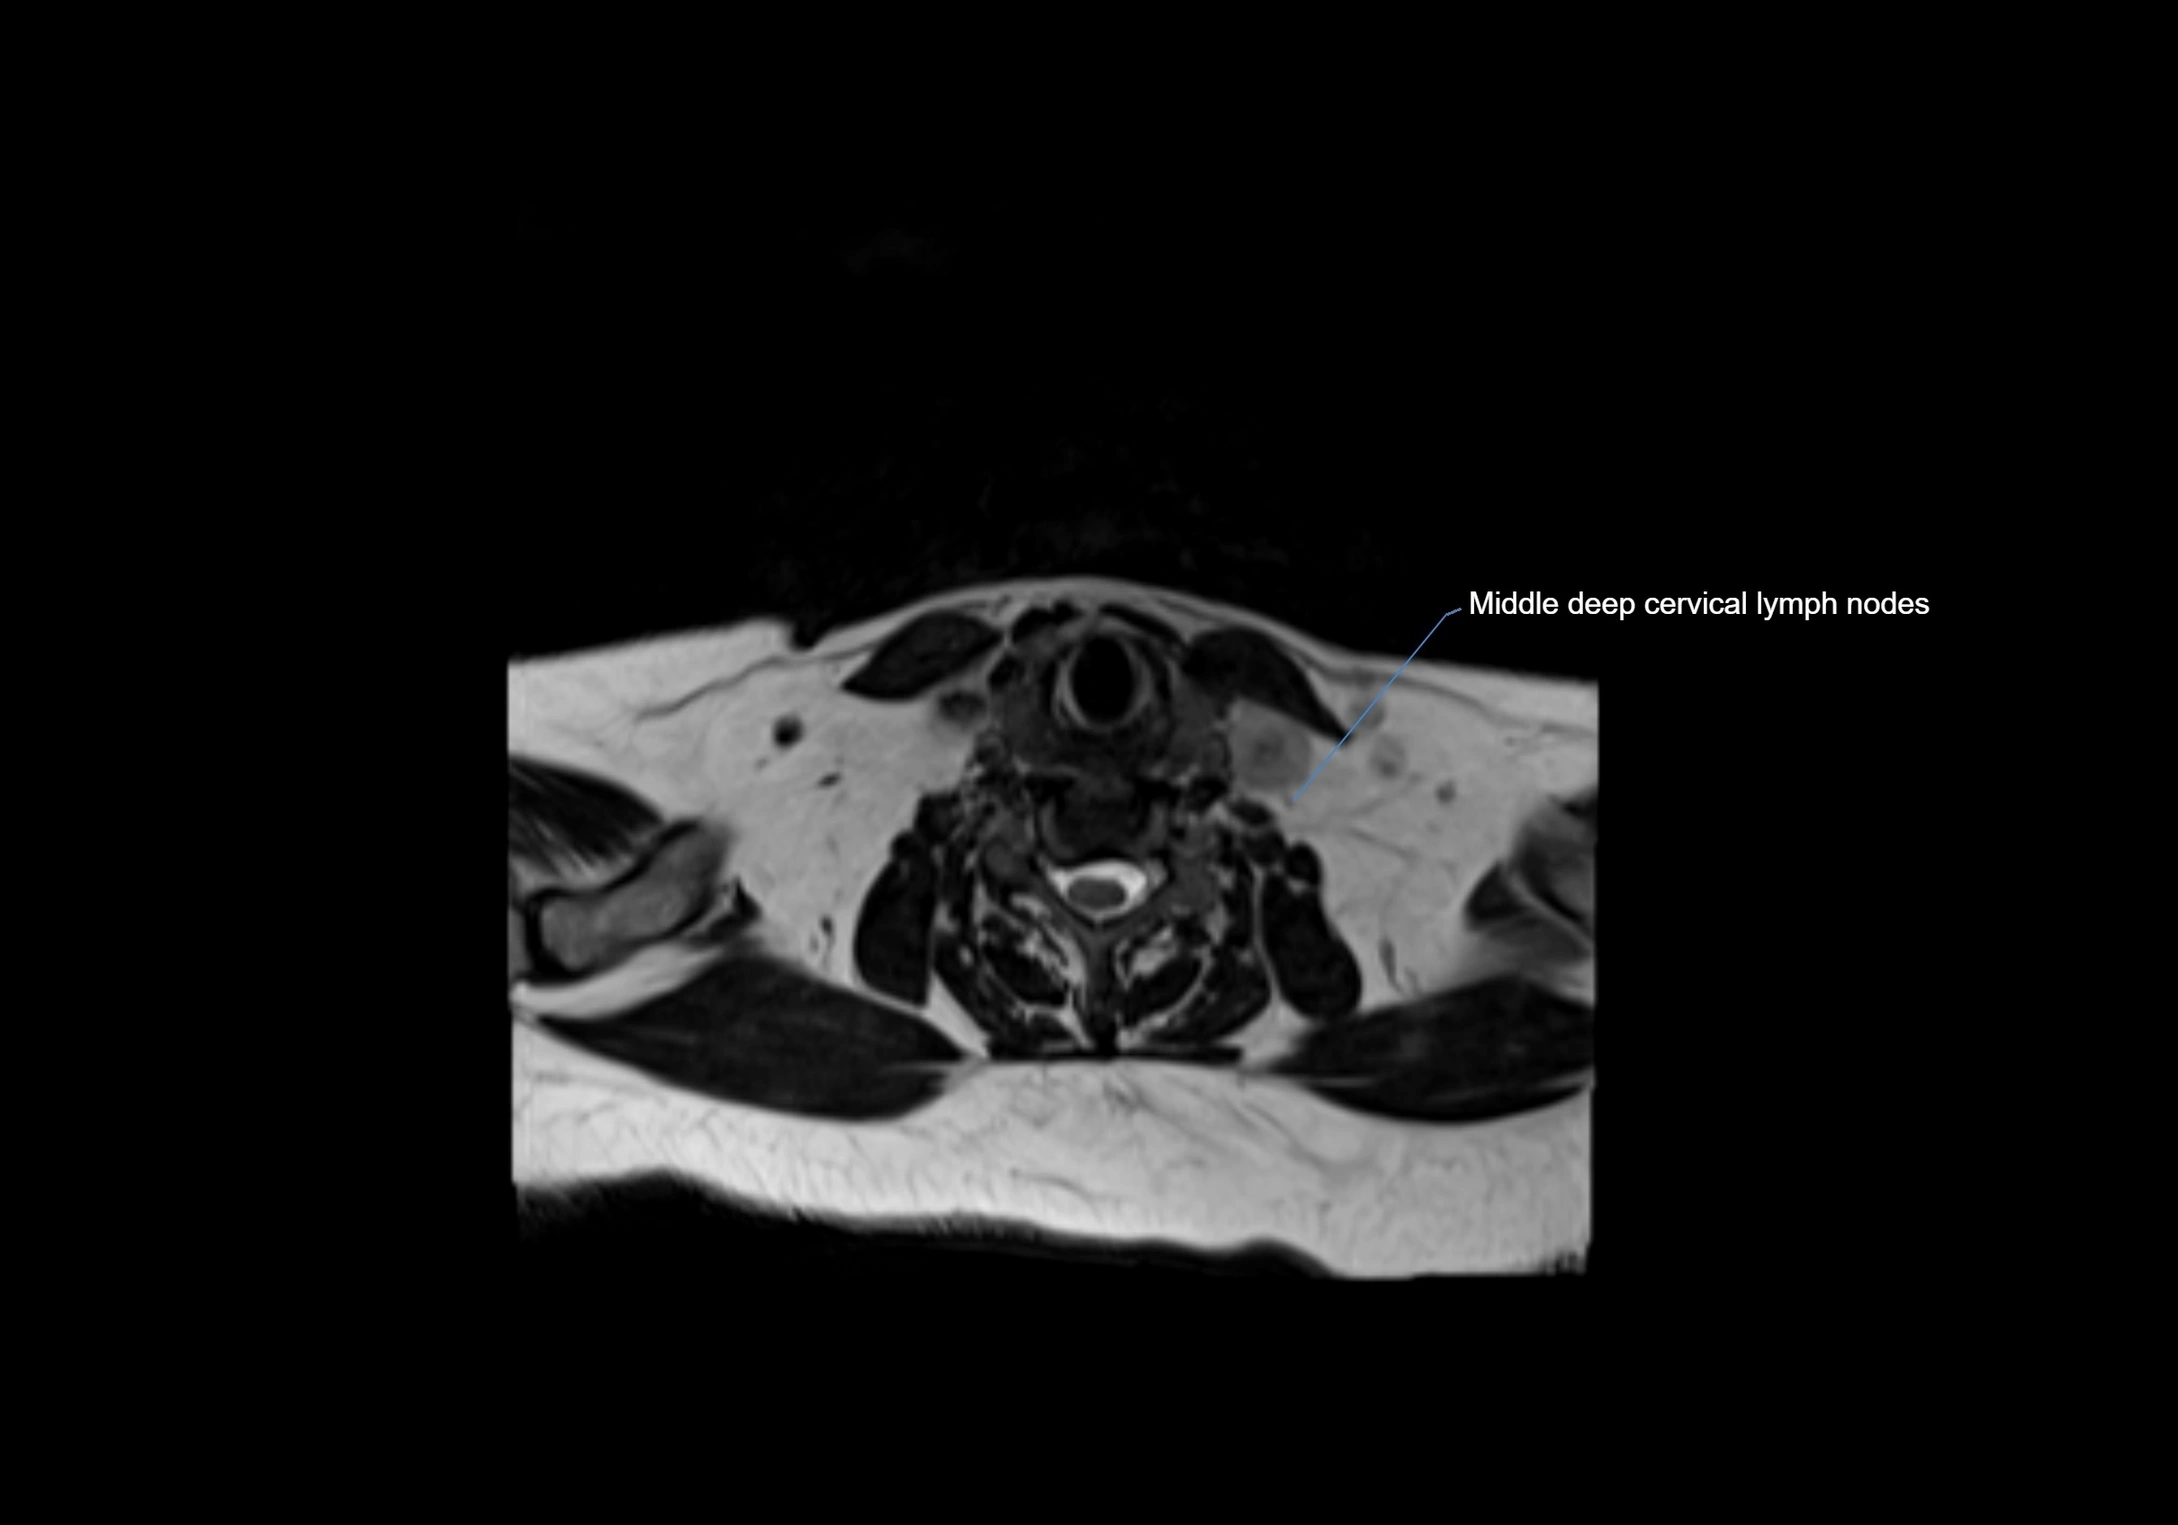

MRI Appearance

T1-weighted images:

• Normal accessory nodes appear as small, oval hypointense to intermediate signal structures within subcutaneous fat

• Surrounded by hyperintense fat, enhancing contrast for visualization

• Pathological nodes may appear enlarged or rounded, sometimes with cortical thickening

T2-weighted images:

• Nodes show intermediate signal, with surrounding fat bright

• Useful for detecting edema, inflammation, or infiltration

• Fatty hilum may appear slightly hyperintense relative to cortex

MRI images

image